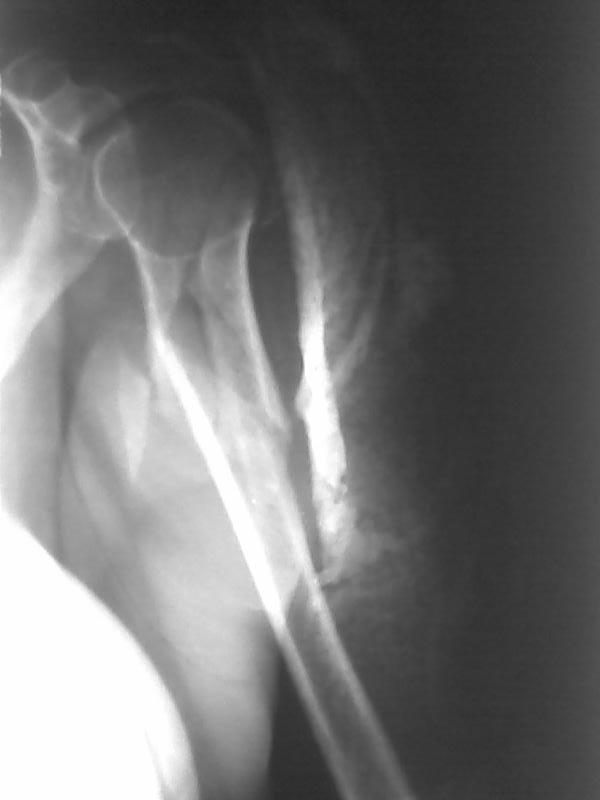

Высылаю рентгенограммы больной до операции и в гипсовой лонгете. Сейчас больную вообщем-то особо ничего не беспокоит, незначительная болезненность в области перелома при движениях плечом, первые два дня была отечность кисти, которая сейчас исчезла, объем движений в локтевом суставе постепенно увеличивается, отведение плеча пока небольшое. Дистальное блокирование выполнено одним винтом в передне-заднем направлении (через бицепс. Да, клинок мы конечно же заблокировали концевым колпачком. Нас тоже беспокоит возможность развития импиджмент синдрома, надеемся на то, что больная разработает движения в плечевом суставе.